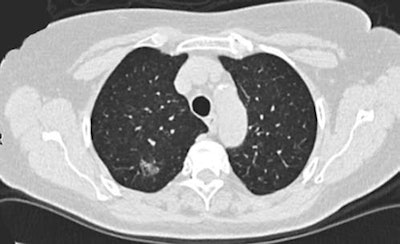

CT screening detected a part-solid  ground-glass opacity nodule from the Danish Lung Cancer Screening Trial. Final diagnosis was adenocarcinoma. All images courtesy of Dr. Jesper Pedersen.

CT screening detected a part-solid  ground-glass opacity nodule from the Danish Lung Cancer Screening Trial. Final diagnosis was adenocarcinoma. All images courtesy of Dr. Jesper Pedersen."With the increasing rate of detection of early lung cancer through screening [low-dose CT] LDCTs, surgeons will be called to provide the necessary expertise to obtain both diagnosis and treatment of screen-detected nodules," the authors stated.